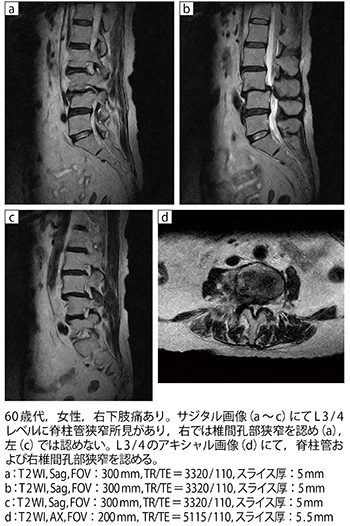

■症例2:腰部脊柱管狭窄症(L3変性すべり)